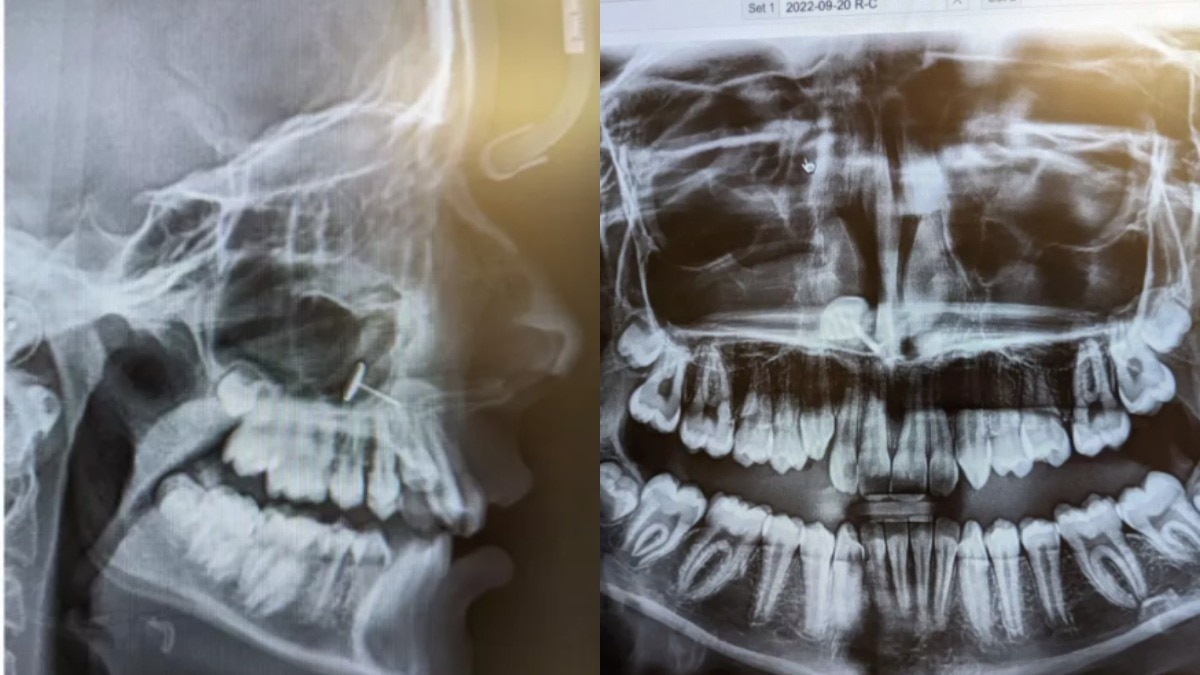

न्यूजवीक की खबर के मुताबिक, ओफीलिया (बदला हुआ नाम) अपनी 13 साल की बेटी को ब्रेसेज की प्रक्रिया शुरू करने के लिए ऑर्थोडॉन्टिस्ट के पास ले गई थीं. यह एक रूटीन विजिट थी, लेकिन एक्स-रे ने सबको चौंका दिया. ओफीलिया ने न्यूजवीक को बताया कि ऑर्थोडॉन्टिस्ट ने एक्स-रे स्क्रीन पर लगाए, और हम सबने एक साथ देखा. कई मिनट तक हम समझ ही नहीं पाए कि ये क्या है.

स्क्रीन पर साफ दिख रहा था कि बेटी की साइनस में धातु का एक छोटा टुकड़ा फंसा हुआ था. मां के लिए यह पूरी तरह रहस्य था, लेकिन उनकी बेटी तुरंत समझ गई कि यह क्या है और वहां कैसे पहुंचा.